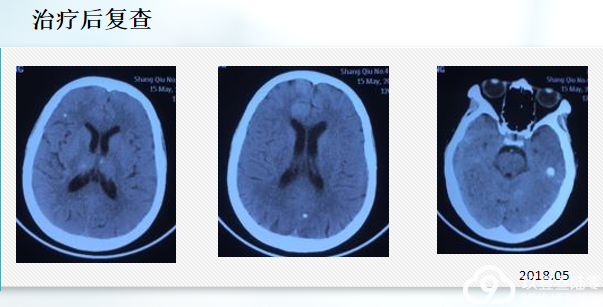

2018年5月16日,确诊腺癌18个月,出现头疼,纳差,呕吐10天,大小便失禁1天,再次入院,查体意识模糊、嗜睡状态,四肢机体不能配合。

2018年5月22日 口服奥希替尼 80mg qd降颅压,应用激素及对症支持治疗 唑来膦酸 4mg q28天

2018年5月22日,服药第二天,神志转轻、呕吐停止,头疼明显减轻,能进食,第三天可下床活动。

2018年6月1日出院。

由于经济原因,患者于2018年7月22日自行停药。停药30天后,出现头痛,走路不稳,改为口服安罗替尼进行治疗,服药两周无效,停止服用安罗替尼。

2018年9月8日,因反应迟钝4月余,加重1月,不能行走15天再次入院。由于疾病进展,患者停药50天后,于2018年9月11日继续服用奥希替尼进行治疗。